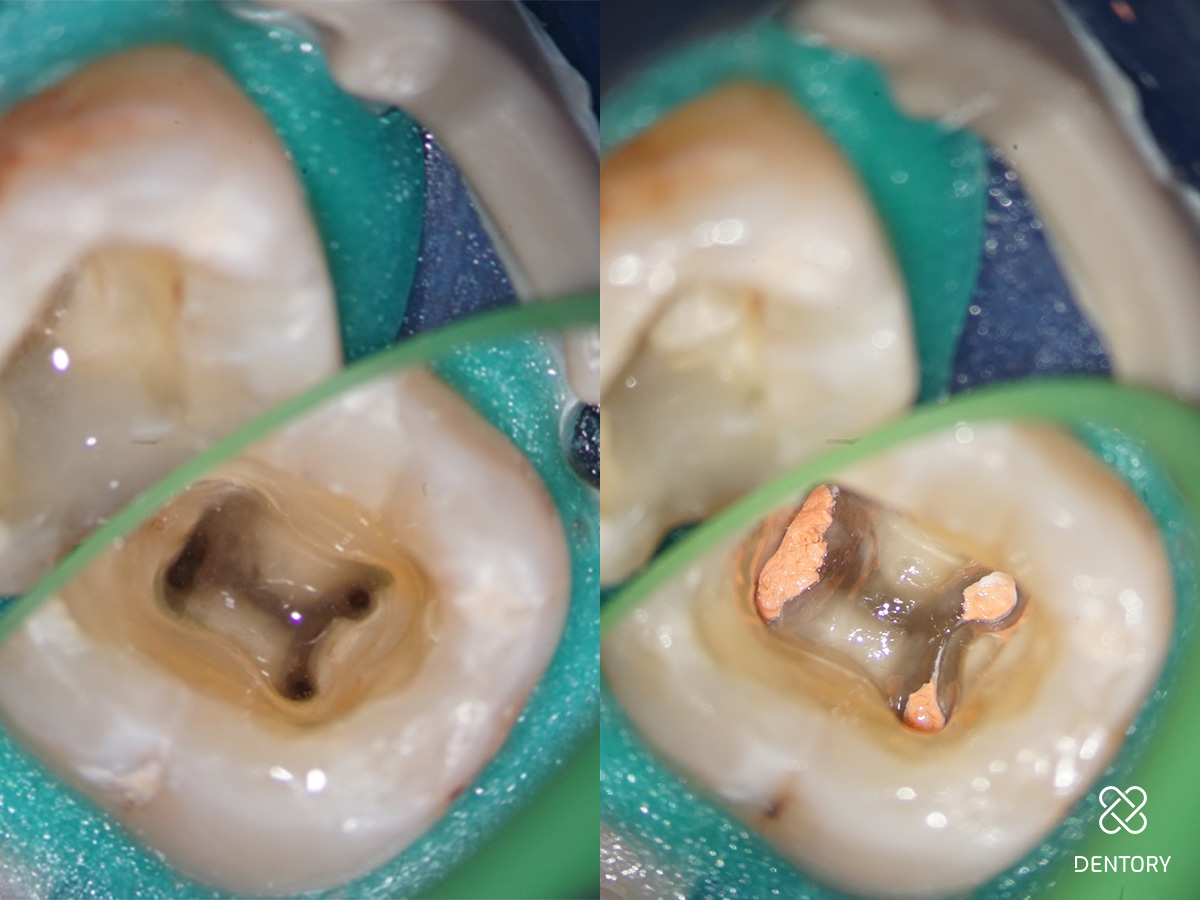

Abbildung 13

Aufnahme vor und nach der Wurzelfüllung; anschließend Applikation des Kompositverschlusses.